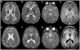

Leukoencephalopathy - thalamus and brainstem anomalies - high lactate

Brainstem anomaly

High lactate

Thalamus anomaly